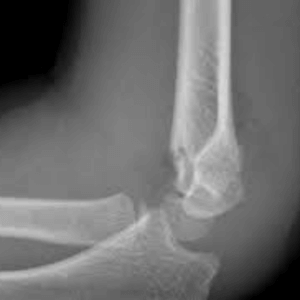

Supracondylar Fracture

Medial Epicondylar Fractures